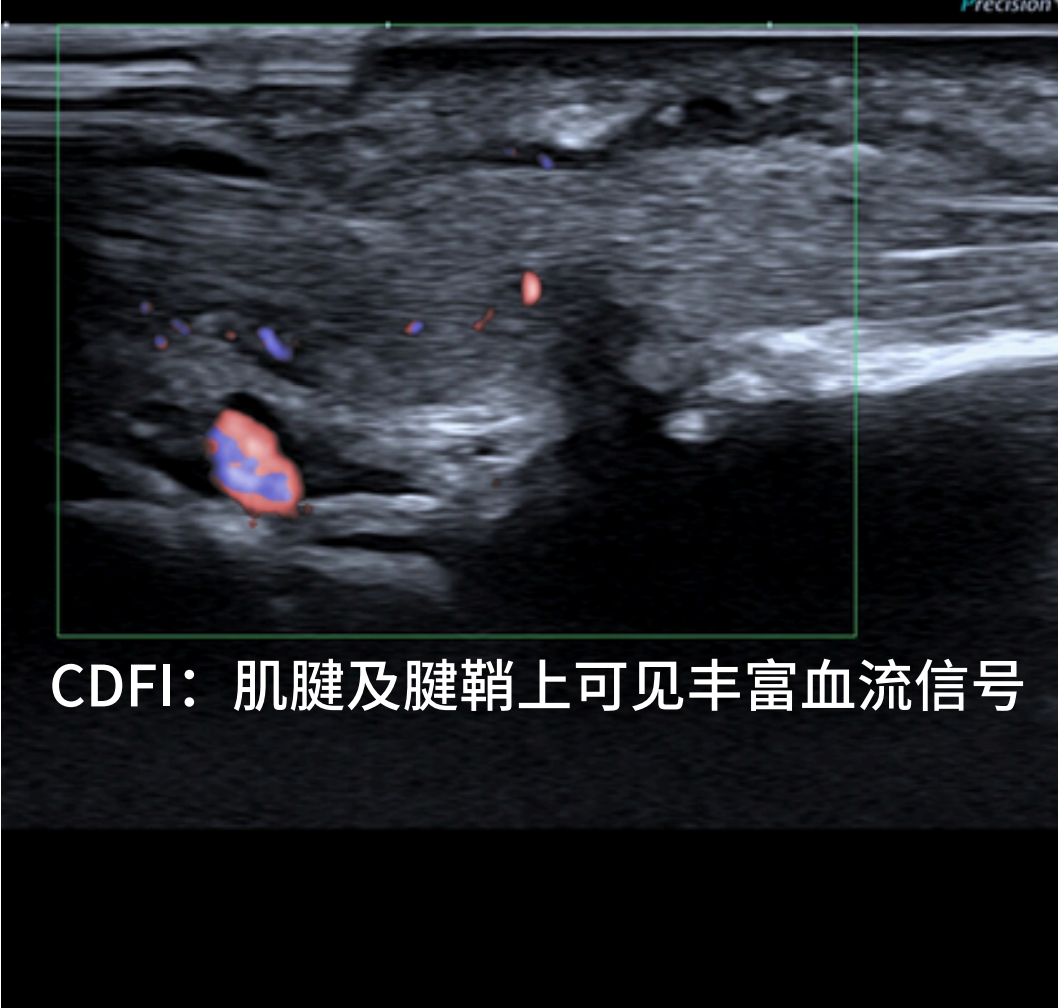

正常情况下,腱鞘厚度 <1 mm,可观察到肌腱在腱鞘内顺畅滑动,无腱鞘积液,CDFI 示肌腱及腱鞘内无明显血流信号。

CDFI 见增厚肌腱及腱鞘内血流信号明显增多